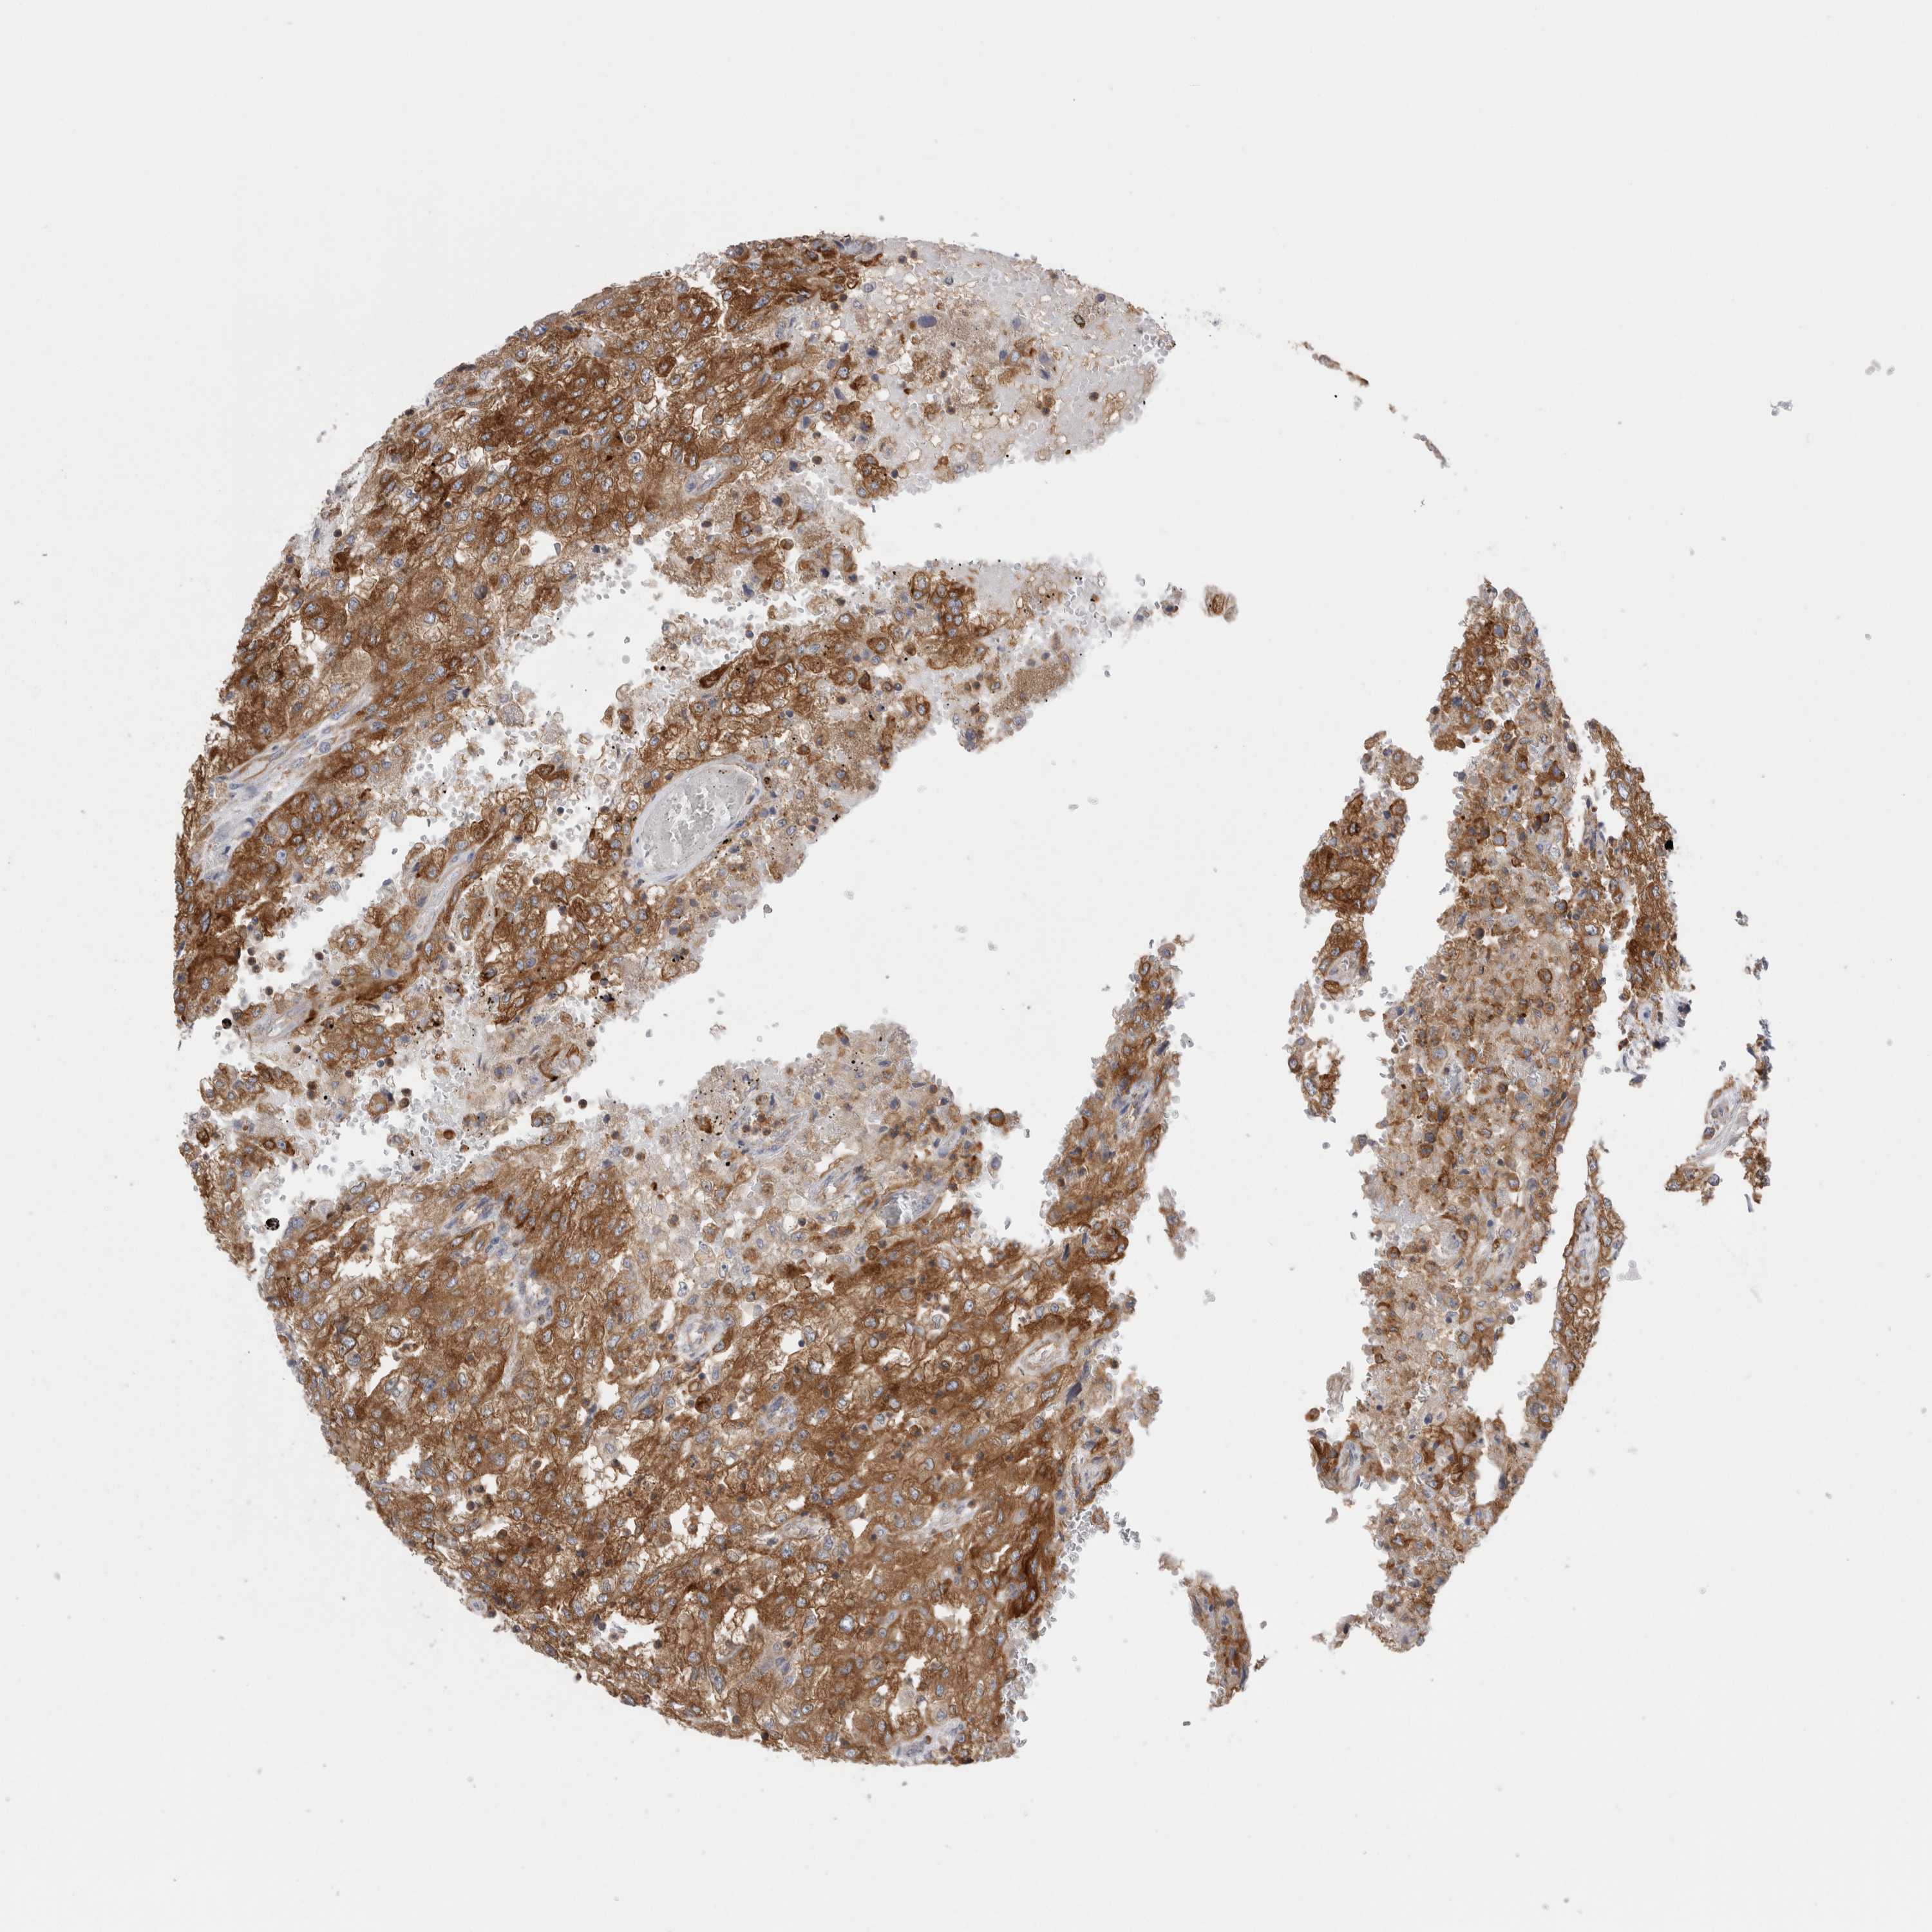

KIDNEY RENAL CLEAR CELL CARCINOMA (VALIDATION) - Interactive survival scatter ploti

The Survival Scatter plot shows the clinical status (i.e. dead or alive) for all individuals in the patient cohort, based on the same data that underlies the corresponding Kaplan-Meier plots. Patients that are alive at last time for follow-up are shown in blue and patients who have died during the study are shown in red.

The x-axis shows the expression levels (FPKM) of the investigated gene in the tumor tissue at the time of diagnosis. The y-axis shows the follow-up time after diagnosis (years). Both axes are complimented with kernel density curves demonstrating the data density over the axes. The top density plot shows the expression levels (FPKM) distribution among dead (red) and alive patients (blue). The right density plot shows the data density of the survived years of dead patients with high and low expression levels respectively, stratified using the cutoff indicated by the vertical dashed line through the Survival Scatter plot. This cutoff is automatically defined based on the FPKM cutoff that minimizes the p-score. The cutoff can be changed by dragging the vertical line or by entering a cutoff value in the square labeled "Current cut-off".

Under the Survival Scatter plot the p-score landscape (black curve; left axis) is shown together with dead median separation (red curve; right axis). Dead median separation is the difference in median mRNA expression between patients who have died with high and low expression, respectively. It is calculated as follows: median FPKM expression of dead patients with high expression - median FPKM expression of dead patients with low expression. This is intended to aid the user in visually exploring custom cutoffs and the associated p-scores and dead median separation.

Individual patient data is displayed and can be filtered by clicking on one or more of the category buttons on the top of the page. Categories describing expression level and patient information include: high, low, alive, dead, female, male and tumor stages. The scale of the x-axis can be toggled between linear and log-scale by clicking on the "x log" button. Mouse-over function shows TCGA ID, patient information and mRNA expression (FPKM) for each patient.

& Survival analysisi

Kaplan-Meier plots summarize results from analysis of correlation between mRNA expression level and patient survival. Patients were divided based on level of expression into one of the two groups "low" (under cut off) or "high" (over cut off). X-axis shows time for survival (years) and y-axis shows the probability of survival, where 1.0 corresponds to 100 percent.

RAB11FIP1 is not prognostic in Kidney Renal Clear Cell Carcinoma (validation)

Best expression cut offi

Based on the FPKM value of each gene, patients were classified into two groups and association between prognosis (survival) and gene expression (FPKM) was examined. The best expression cut-off refers the FPKM value that yields maximal difference with regard to survival between the two groups at the lowest log-rank P-value. Best expression cut-off was selected based on survival analysis .

When clicking on this number, the vertical dashed line indicating cut-off, the interactive survival plot, and the Kaplan-Meier curve will be adjusted to show results based on the best expression cut-off.

: 16.44

Median expressioni

Median expression refers to the median FPKM value calculated based on the gene expression (FPKM) data from all patients in this dataset. When clicking on this number, the vertical dashed line indicating cut-off, the interactive survival plot, and the Kaplan-Meier curve will be adjusted to show results based on the median expression.

: N/A

Median follow up timei

Median follow up time refers to the median time (years) after diagnosis with this type of cancer, based on clinical data from all patients in this dataset.

P scorei

Log-rank P value for Kaplan-Meier plot showing results from analysis of correlation between mRNA expression level and patient survival.

N/A

5-year survival highi

5-year survival for patients with higher expression than the expression cutoff.

For melanoma and glioma, 3-year survival is shown.

5-year survival lowi

5-year survival for patients with lower expression than the expression cutoff.

TCGA RNA samplesi

RNA-seq data is reported as average FPKM (number Fragments Per Kilobase of exon per Million reads), generated by the The Cancer Genome Atlas (TCGA) .

Normal distribution across the dataset is visualized with box plots, shown as median and 25th and 75th percentiles. Points are displayed as outliers if they are above or below 1.5 times the interquartile range. FPKM values of the individual samples are presented next to the box plot.

Average pTPM 18.3

Number of samples 100